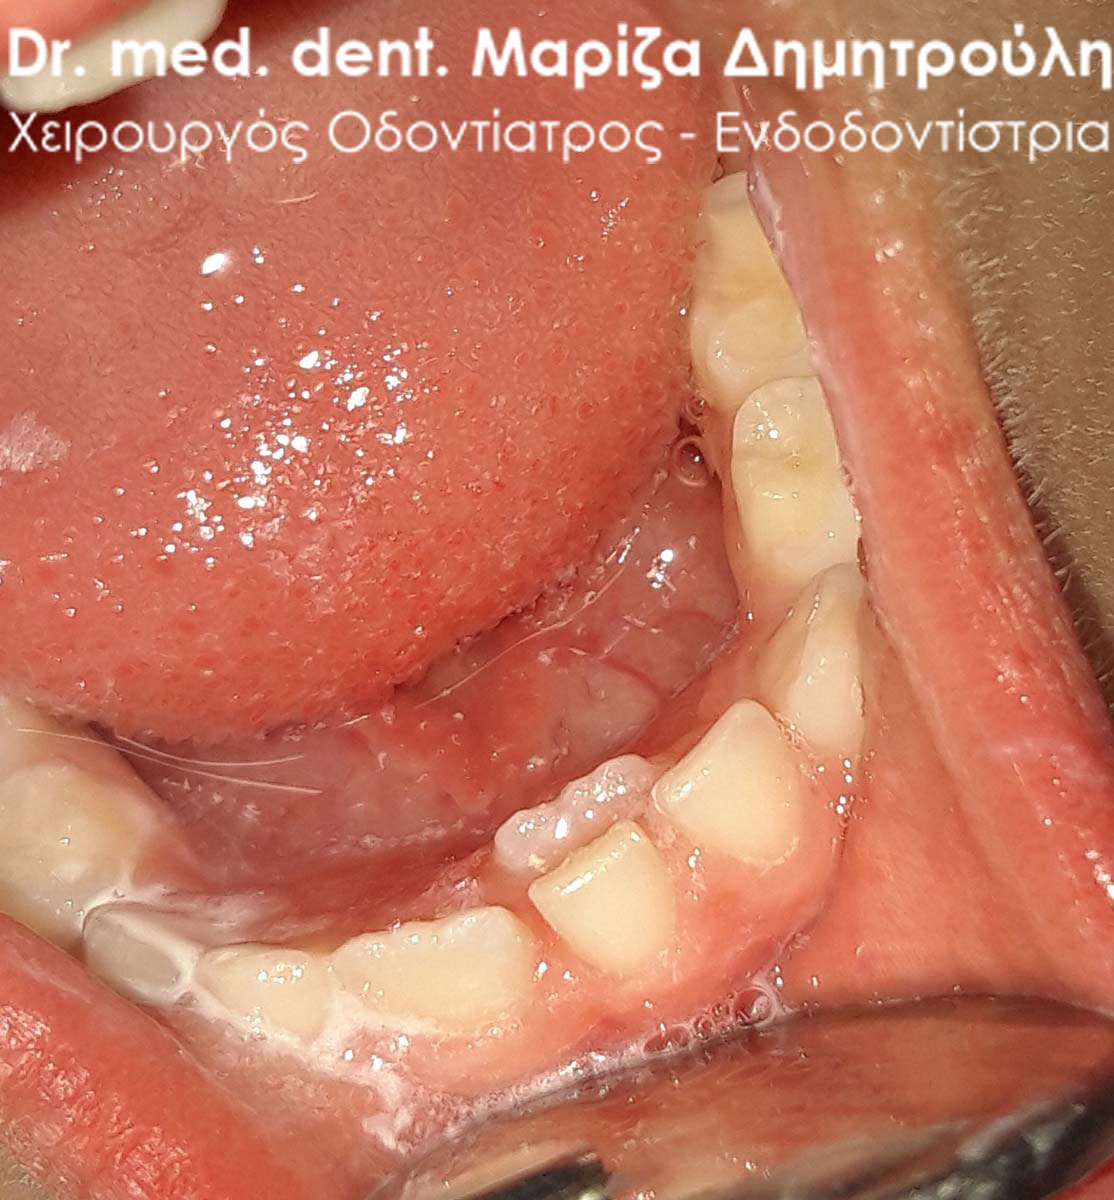

Το παιδικό δοντάκι στη μικρή ασθενή είχε παραμείνει στη θέση του, ενώ είχε κάνει την εμφάνιση του το αντίστοιχο μόνιμο δόντι. Η φωτογραφία δείχνει την εικόνα του στόματος του κοριτσιού αμέσως μετά την εξαγωγή του νεογιλού τομέα. Το μόνιμο δοντάκι που βρισκόταν πίσω από το αντίστοιχο νεογιλό θα πάρει την τελική του θέση μέσα στο στόμα του παιδιού σε διάστημα 3 – 4 εβδομάδων.